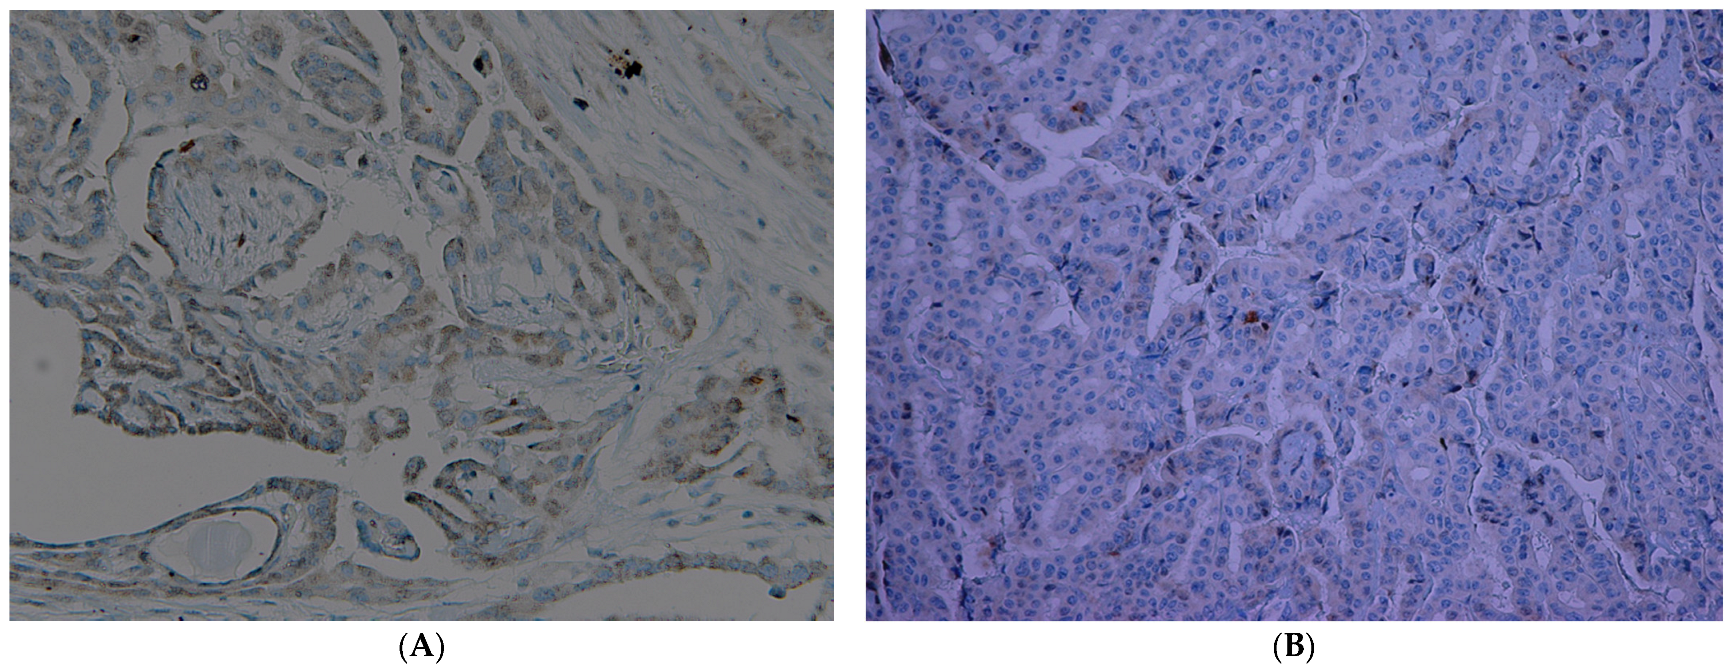

| Neoplastic Cells | Thyrocytes | Inflammatory Cells | |

|---|---|---|---|

| Thyroid Cancer | +++c/focal n | +c/-n | -c/-n |

| HT | - | +c/-n | -c/-n |

| Adenomas | ++c/focal n | +c/-n | -c/-n |

| Thyroid Cancer | +c/+n | +++c/+n | +c/+++n |

| HT | - | focal c/++n | focal c/+++n |

| Adenomas | ++c/+n | +c/+n | -c/focal n |